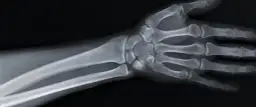

RTG dłoni pozwala ocenić zmiany w strukturze kości i stawów. Badanie to jest szczególnie ważne przy podejrzeniu choroby zwyrodnieniowej.

- RTG dłoni